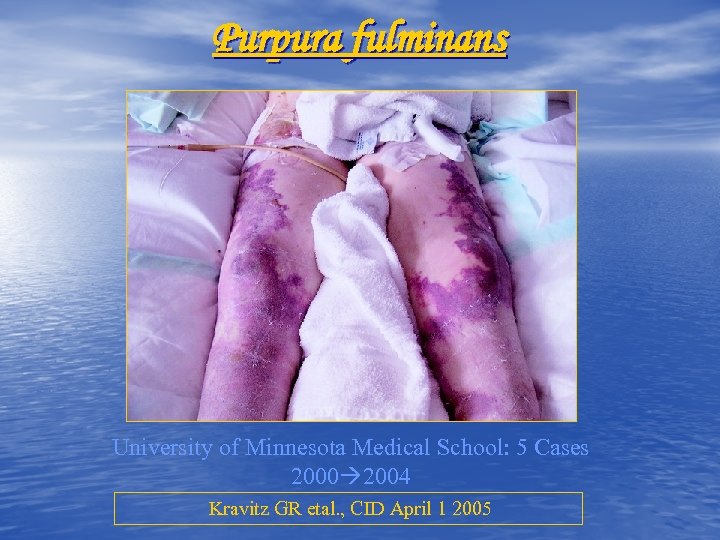

Purpura fulminans University of Minnesota Medical School: 5 Cases 2000 2004 Kravitz GR etal. , CID April 1 2005

Purpura fulminans University of Minnesota Medical School: 5 Cases 2000 2004 Kravitz GR etal. , CID April 1 2005

Purpura fulminans University of Minnesota Medical School: 5 Cases 2000 2004 Kravitz GR etal. , CID April 1 2005

Purpura fulminans University of Minnesota Medical School: 5 Cases 2000 2004 Kravitz GR etal. , CID April 1 2005